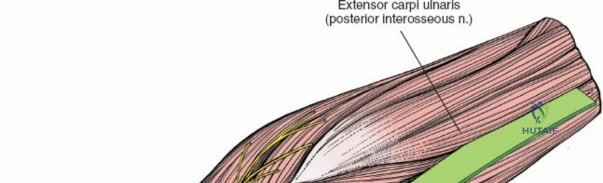

The Posterior Interosseous Nerve (PIN)

The posterior interosseous nerve is the single most important structure left vulnerable during exposure of the proximal radius. A branch of the radial nerve, the PIN dives into the supinator muscle through the Arcade of Frohse. It travels obliquely and spirally around the radial neck and proximal shaft within the substance of the supinator. In approximately 25% of patients, the nerve comes into direct contact with the posterior periosteum of the radial neck. Therefore, any blind placement of retractors around the posterior aspect of the proximal radius is strictly contraindicated, as it can easily crush the nerve against the bone, resulting in devastating loss of finger and thumb extension.

The proximal radius is draped by the supinator muscle. The PIN passes directly through the belly of the supinator. To protect the nerve, the forearm must be fully supinated. Supination dynamically rotates the radius, carrying the insertion of the supinator anteriorly and simultaneously displacing the PIN laterally and posteriorly, safely away from the surgical field.

With the forearm fully supinated, identify the broad insertion of the supinator on the anterior aspect of the radius. Incise the supinator directly along the line of its insertion onto the bone. It is critical to detach the muscle by dividing its insertion sharply at the bone, rather than splitting the muscle belly, which would risk cutting the PIN.

Proceed with strict subperiosteal dissection, elevating the supinator laterally off the bone. This is one of the rare instances in orthopedic surgery where the safety gained by staying in a subperiosteal plane completely outweighs the theoretical vascular damage to the bone caused by periosteal stripping. The elevated supinator muscle belly now acts as a protective cushion for the PIN.